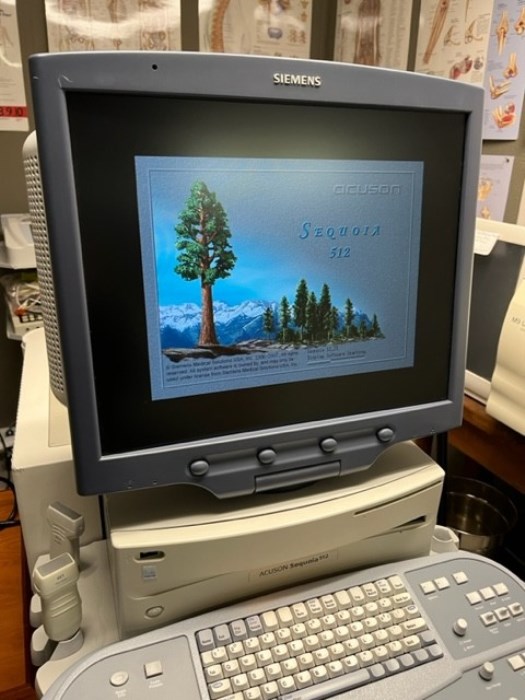

Siemens Sequioa Ultrasound

Pre-owned. In good working condition. Shown as is. Siemens Sequoia Ultrasound. DOM: 2006

Probes: 15L8w, 4V1, 10V4, 6L3, 4C1